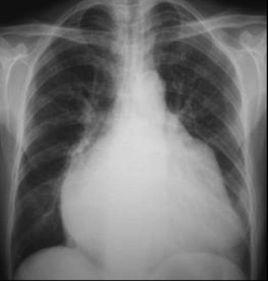

左心房顯著增大時,胸骨左緣第3肋間心濁音界擴大,使心腰消失。當左心房與肺動脈段均擴大時,胸骨左緣第2、3肋間心濁音界向外擴大,心腰部更為飽滿或膨出,使心濁音界呈梨形。因其常見於二尖瓣狹窄,又稱二尖瓣型心。二尖瓣狹窄時,舒張期血液由左房進入左室受阻,血液在左心房內瀦留,使心房內壓力和負荷異常增高,左房發生代償性擴大與肥厚,肺動脈高壓及擴張,右心室肥厚及擴大,使得主動脈弓縮小,肺動脈主幹突出,左心房增大,右心室增大,心臟呈梨形。

X線表現:

後前位:出現雙房影,左心耳隆凸。